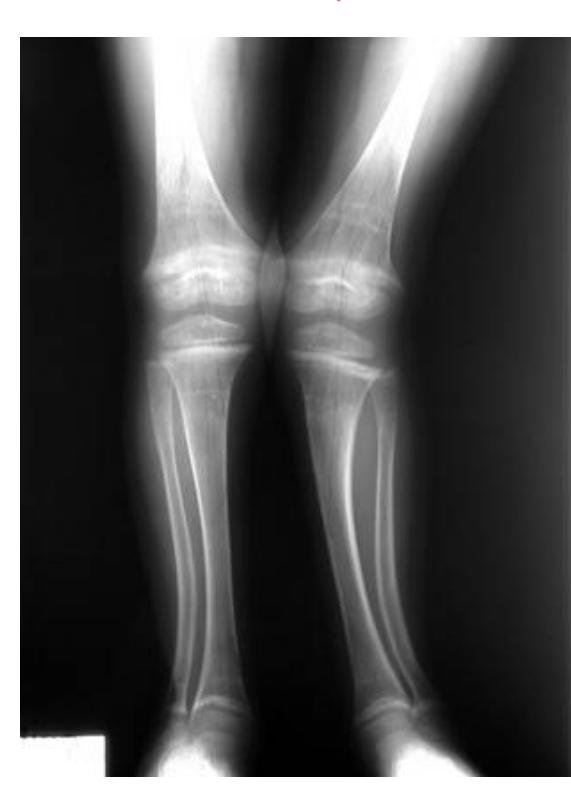

Rickets

Radiological Features

What are the characteristic x-ray findings in rickets?

- Widening of the epiphyseal plate

- Cupping of the metaphysis

- Irregular metaphyseal ends

- Widened physis

Pediatric Case Study

A 5-year-old boy was brought to the clinic because of a progressively increasing deformity in his left leg for 6 months.

What are the abnormal x-ray findings?

- Widening of epiphyseal plate

- Cupping of metaphysis

How will you treat the underlying cause?

- Vitamin D supplementation